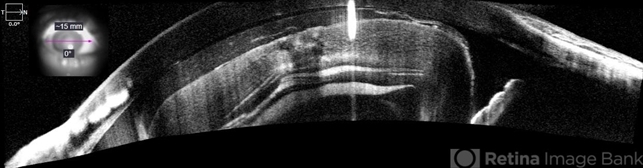

- subluxation of lens, lens luxation, Luxated lens to anterior segment

Optical Coherence Tomography System - OCT CIRRUS 5000, Protocol Wide Angle to Angle.

- Patient 61 years old, Female, subta low vision after blunt trauma. In the anterior segment photograph, the presence of a lens in the anterior chamber is observed. In the previous follow-up OCT, the disorganization of this follow-up is clear. Above all, the documentation of these cases is essential for future decisions. This patient was urgently referred for a surgical procedure, mainly to control the intraocular pressure, which was at 60 IOP.